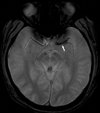

Background and purpose: The purpose of this study was to provide the first correlative study of the hyperdense middle cerebral artery sign (HMCAS) and gradient-echo MRI blooming artifact (BA) with pathology of retrieved thrombi in acute ischemic stroke.

Methods: Noncontrast CT and gradient-echo MRI studies before mechanical thrombectomy in 50 consecutive cases of acute middle cerebral artery ischemic stroke were reviewed blinded to clinical and pathology data. Occlusions retrieved by thrombectomy underwent histopathologic analysis, including automated quantitative and qualitative rating of proportion composed of red blood cells (RBCs), white blood cells, and fibrin on microscopy of sectioned thrombi.

Results: Among 50 patients, mean age was 66 years and 48% were female. Mean (SD) proportion was 61% (±21) fibrin, 34% (±21) RBCs, and 4% (±2) white blood cells. Of retrieved clots, 22 (44%) were fibrin-dominant, 13 (26%) RBC-dominant, and 15 (30%) mixed. HMCAS was identified in 10 of 20 middle cerebral artery stroke cases with CT with mean Hounsfield Unit density of 61 (±8 SD). BA occurred in 17 of 32 with gradient-echo MRI. HMCAS was more commonly seen with RBC-dominant and mixed than fibrin-dominant clots (100% versus 67% versus 20%, P=0.016). Mean percent RBC composition was higher in clots associated with HMCAS (47% versus 22%, P=0.016). BA was more common in RBC-dominant and mixed clots compared with fibrin-dominant clots (100% versus 63% versus 25%, P=0.002). Mean percent RBC was greater with BA (42% versus 23%, P=0.011).

Conclusions: CT HMCAS and gradient-echo MRI BA reflect pathology of occlusive thrombus. RBC content determines appearance of HMCAS and BA, whereas absence of HMCAS or BA may indicate fibrin-predominant occlusive thrombi.